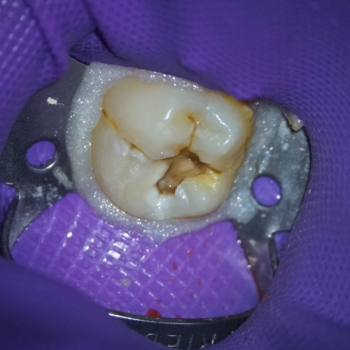

Pacienta s-a prezentat raportând durere de scurtă durată la dintele nr. 19 (Fig. 1). Prin radiografie, o evaluare clinică și o analiză a istoricului clinic al pacientei a fost diagnosticată o leziune carioasă extinsă (Fig. 2) ca și cauză a durerii, ca urmare a unui proces de pulpită reversibilă.

Izolarea a fost realizată folosind o digă de cauciuc, o clemă din oțel inoxidabil și digă lichidă fotopolimerizabilă plasată în jurul clemei pentru a preveni contaminarea bacteriană a zonei de tratat. Caria a fost îndepărtată circumferențial de la marginea coronară spre marginea cervicală pentru a limita intrarea bacteriilor în spațiul țesutului pulpar (9). O explorare a podelei cavității a arătat o expunere a pulpei (Figurile 3 și 4). Este întotdeauna recomandabil să explorați podeaua cavității cu un endoexplorator, deoarece o deschidere mică a camerei pulpare poate fi trecută cu vederea.

Fig. 1. Dintele nr. 19 cu carie profundă. Izolarea totală înainte de îndepărtarea cariei.

Fig. 3. & Fig. 4. Expunerea pulpară la nivelul podelei cavității, cu hemoragie minimă ușor de controlat.